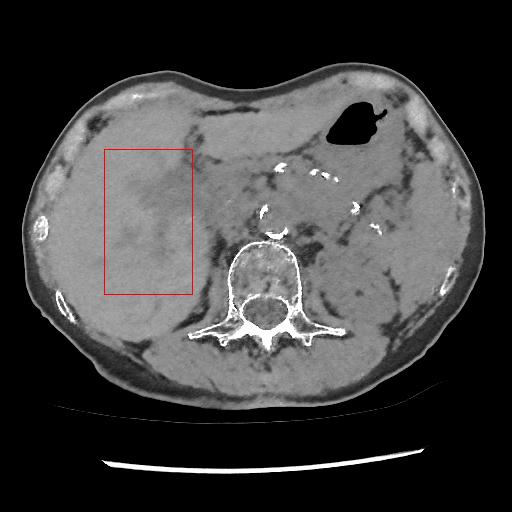

This section systemically investigates the efficacy of every module proposed in this study. We considered three different networks; first, baseline model(M1), where the inverting block is replaced with dense block, and trained using minimizing mean square distance between two noisy observations(i.e. fsubscript𝑓\mathcal{L}_{f}). Next, two independent baseline model(one for forward mapping, one for reverse mapping) is jointly trained using a linear combination fsubscript𝑓\mathcal{L}_{f}, and rsubscript𝑟\mathcal{L}_{r}, similar to cycle consistent network paradigm. The forward mapping network is used for testing. We refer this model as M2. In both M1, and M2, we increased the depth of the network to make the representation power of these networks comparable with inverting network. Finally, the proposed method, referred as M3. Table 2 depicts the objective evaluation of the three networks using the D1 dataset. Both M2 and M3 use reverse mapping to regularize the network; the influence of the same in the denoising performance is evident from Table 2. Adding cycle consistency loss has improved the performance of the same baseline model significantly. The inverting network performed considerably better than the network M2. It improves PSNR by 0.23dB. As discussed in the above section, in case cycle consistency loss, an additional network is trained, but that does not always guarantee invertibility, whereas inverting network architecture inherently possesses reversibility, which acts as a strong regularizer. In Figure 3 we have shown denoising performance of different networks visually. To demonstrate the requirement of regularization, we first extract the boundary line of the various organ from the NDCT image and superimpose the boundary line on the output of different networks. As shown in Figure 3, many pixels around the boundary line of M1 network output are missing. Using the reverse mapping, the issue of the end-organ missing pixel is successfully overcome in M2 and M3. The granular pattern is also less present in the M3 than M2. The zoomed version of a ROI taken from the images of Figure 3 is given in Figure 4 for better perception. In Figure 5 we give an example of the performance of the invertible network in reverse mapping. Here, the predicted LDCT image is produced by using the predicted clean image of the forward mapping as the input for reverse mapping. As shown, the predicted noisy pattern is similar to the original noise pattern. The same streaking artifacts are present in both the noise pattern; also, the noise variance is different in the various spatial region depending on the signal intensity of the original CT image. It validates that the loss of information in reverse mapping is minimal. Due to the invertible network’s structural advantage, the network also preserves every information present in the input image in the forward mapping.

Refer to caption

(a) LDCT

(b) BM3D

(c) DIP

(d) CycleGAN

(e) ConsensusNet

(f) Proposed

Figure 9: Comparison of denoising performance of different network. Zoomed view of the region inside the bounding box shown in the images for Figure 8

5.3 Performance on the real low dose CT data

Here, we analyse the performance of the proposed method on clinical data. Since there are no ground truths available, only qualitative comparisons are performed. An example of the denoising performance of the proposed method is given in Figure 8. Here we can see denoising performance of BM3D is the worst compared to other methods. On the other hand, the output of the deep image prior is very blurry, different organ boundary is distorted, and some splotchy artifacts appear in the image. The performance of DIP depends mainly on the stopping iteration; with more iterations, it will again produce the original noisy image. The clean image produced by it is always blurry and without any texture. Consistent with our previous example, we can see CycleGAN has a lot of residual noise left in the example. Next, we identified one hypodense lesion in the image and marked the region with the red colour bounding box. The zoomed version of the region containing the lesion is shown in Figure 9. The effect of denoising is perceptible in this zoomed view. The visibility of the lesion is very inconspicuous in the original LDCT image. The noise variance is very high in this region; consequently, BM3D and CycleGAN failed to remove noise from this region. On the other hand, DIP has removed the noise but also destroyed the image by removing all the texture information. ConsensusNet also produced a blurry version of the lesion in the output. At the same time, our method produced a denoised image with the lowest granular pattern and improved the lesion’s visibility. The main objective of image denoising is to restore the visibility of these types of lesions and anomalies by concealing the noise. In this regard, our method has reached the goal as the perceptibility of different anomalies has been improved vastly without losing structural or textural information.